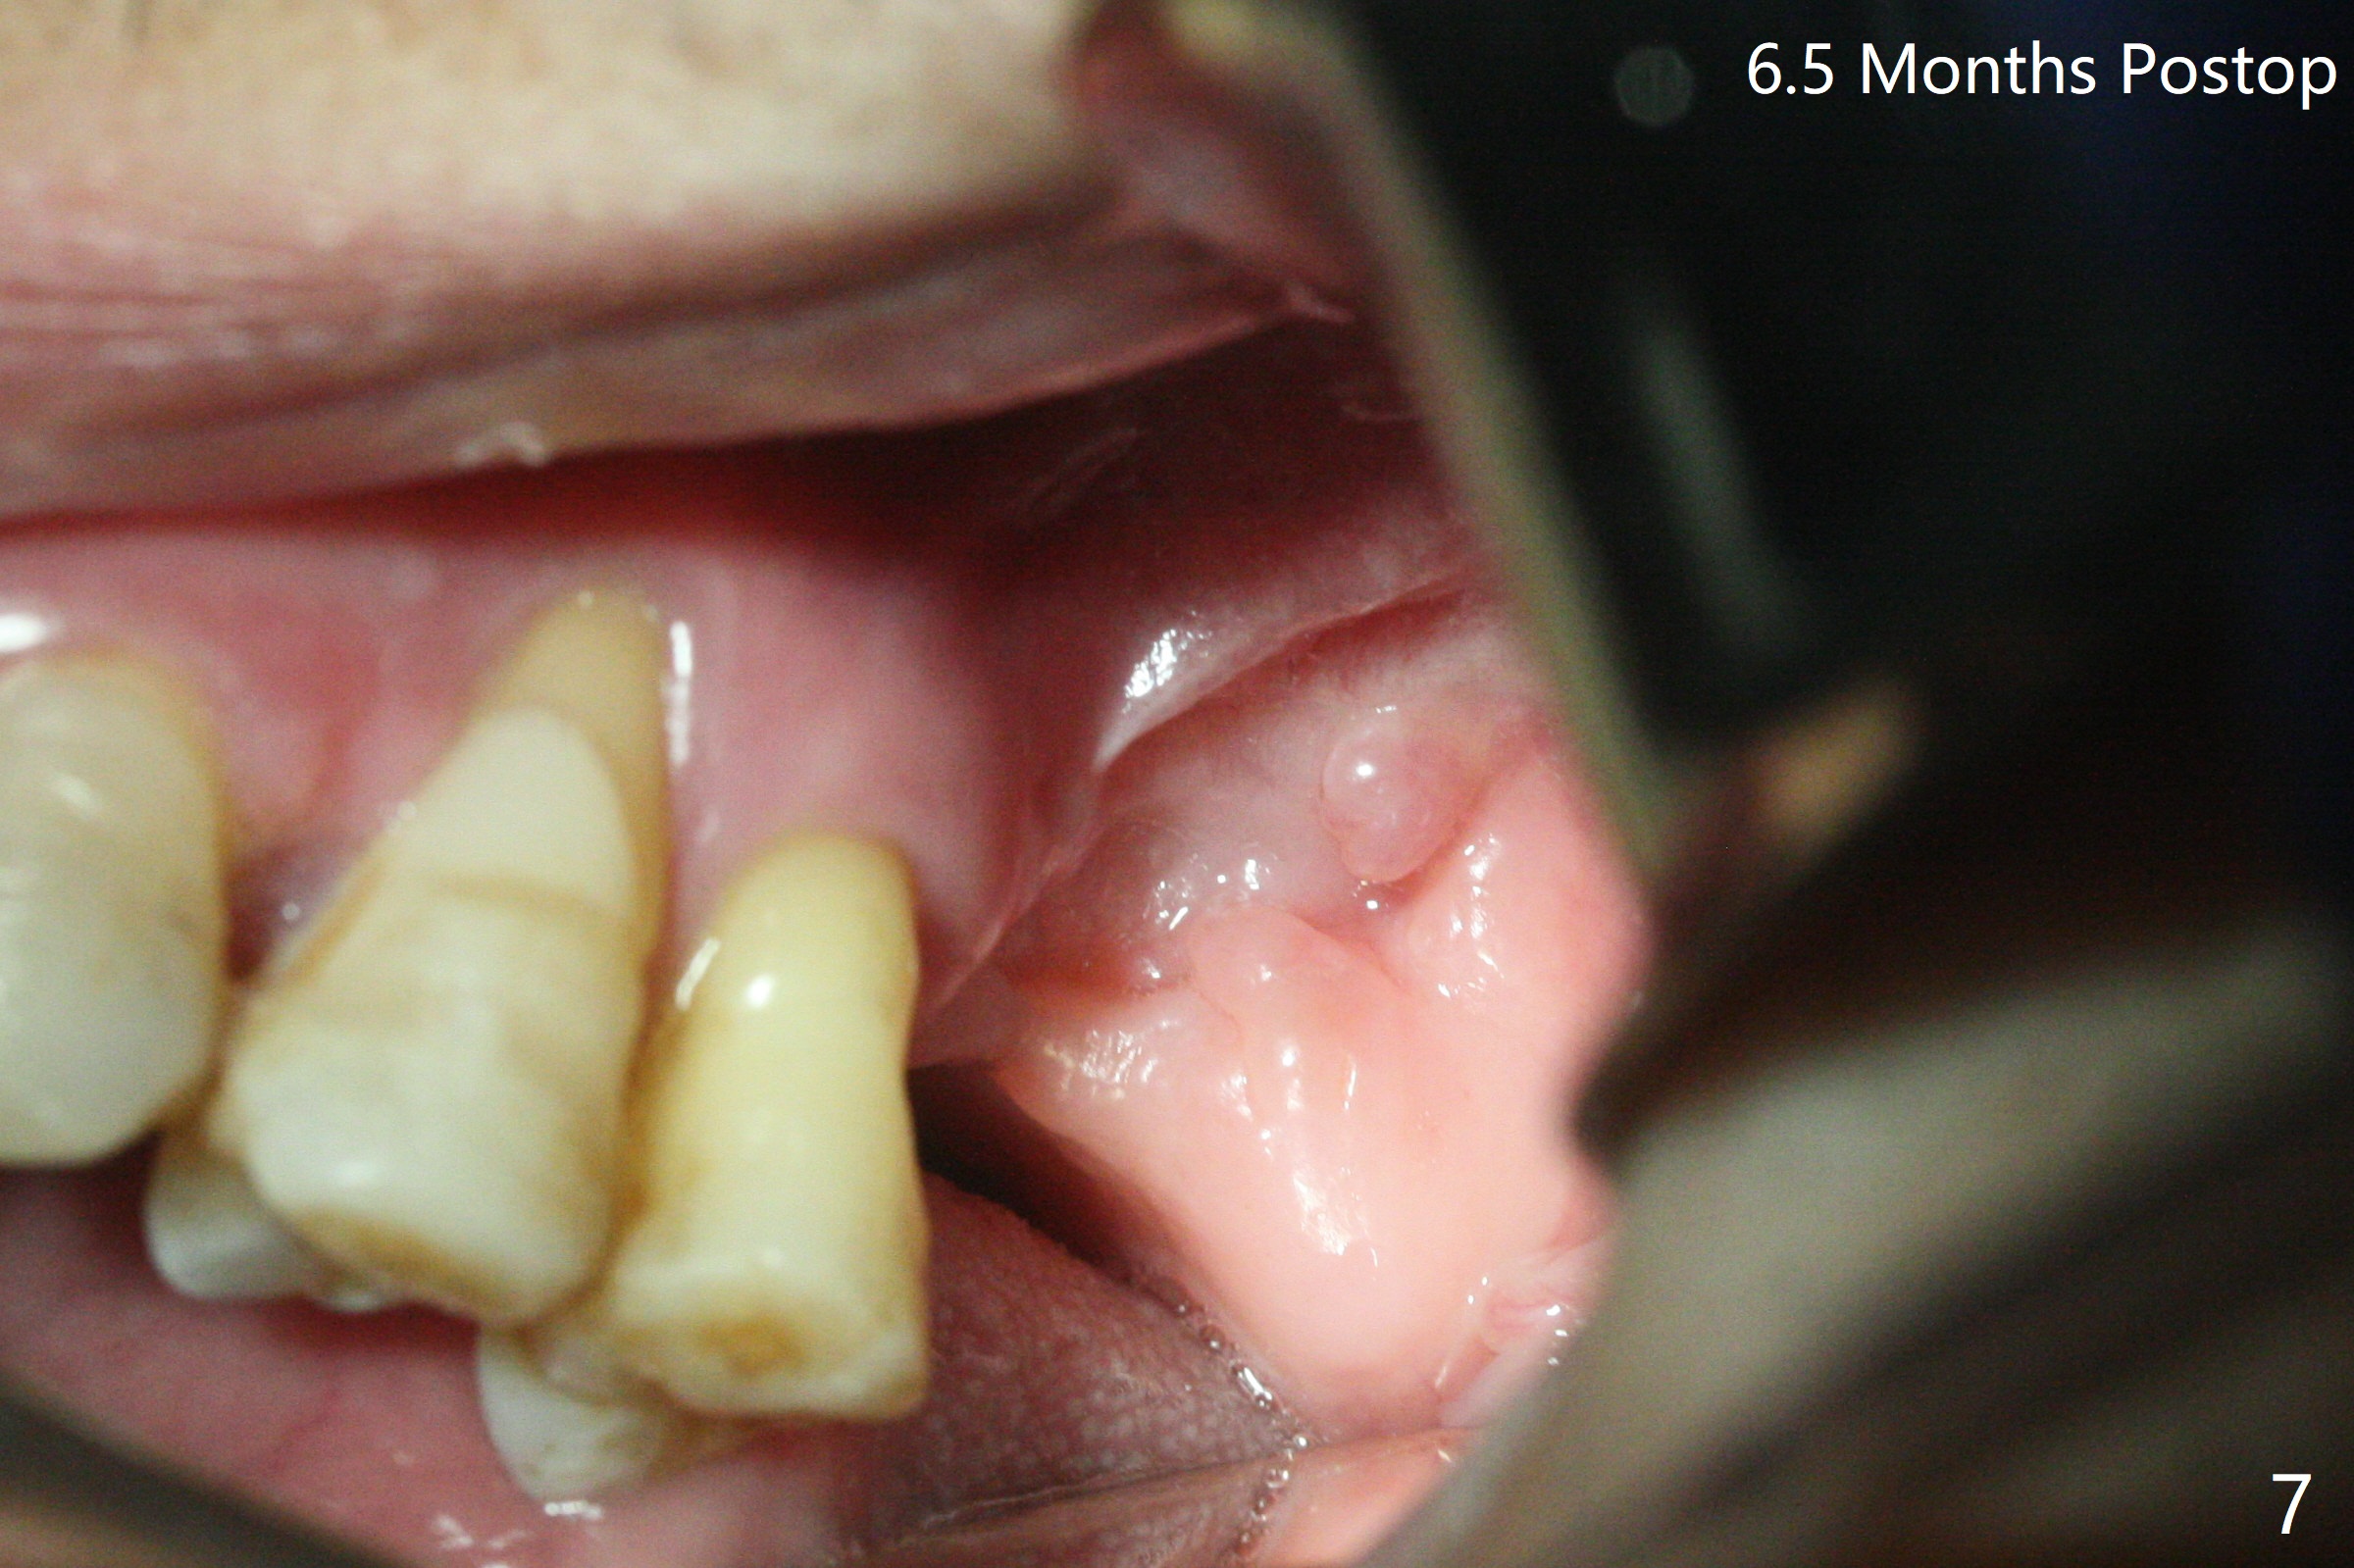

47岁男原本回诊所拔除近中左上智齿(16号牙),影响第一磨牙(14号牙)植牙周围炎治疗后卫生维护。事先制备PRF(图一,二)和骨块(图三 *),拔牙顺利,发现植牙螺纹依然暴露,决定取出植体,上颌窦底板缺失,但膜仿佛完整,放置一小块PRF于上颌窦底,促进上颌窦膜愈合,然后加入新的骨粉,与剩余上清液(图三 >)调袢,虽然不再形成粘性骨块,但是还有好处,放置于拔牙窝以及植牙窝(图四 *),浅部放置骨块(S),这样骨粉不容易丢失,表面再放置PRF膜和不可吸收膜(Cytoplast),使用PTFE缝线。术后7周Cytoplast几乎完全暴露(图五)。当它取出后,骨粉好像损失不少(图六)。二个月后再评价。术后6.5月第一磨牙区仍萎缩(图七),只好再植骨,在第三磨牙区安置一个tenting screw,也在第一磨牙区植入第二个钉子,但是不牢靠,因为仍处于纤维状,把它往上颌窦推作为上颌窦粘膜(图八:>),然后提升(*)。在第一,第三磨牙交界处打入第二个帐篷钉,在两个钉子周围放置粘性骨粉,覆盖PRF膜,缝合。估计植骨效果不佳,植牙时再植骨。